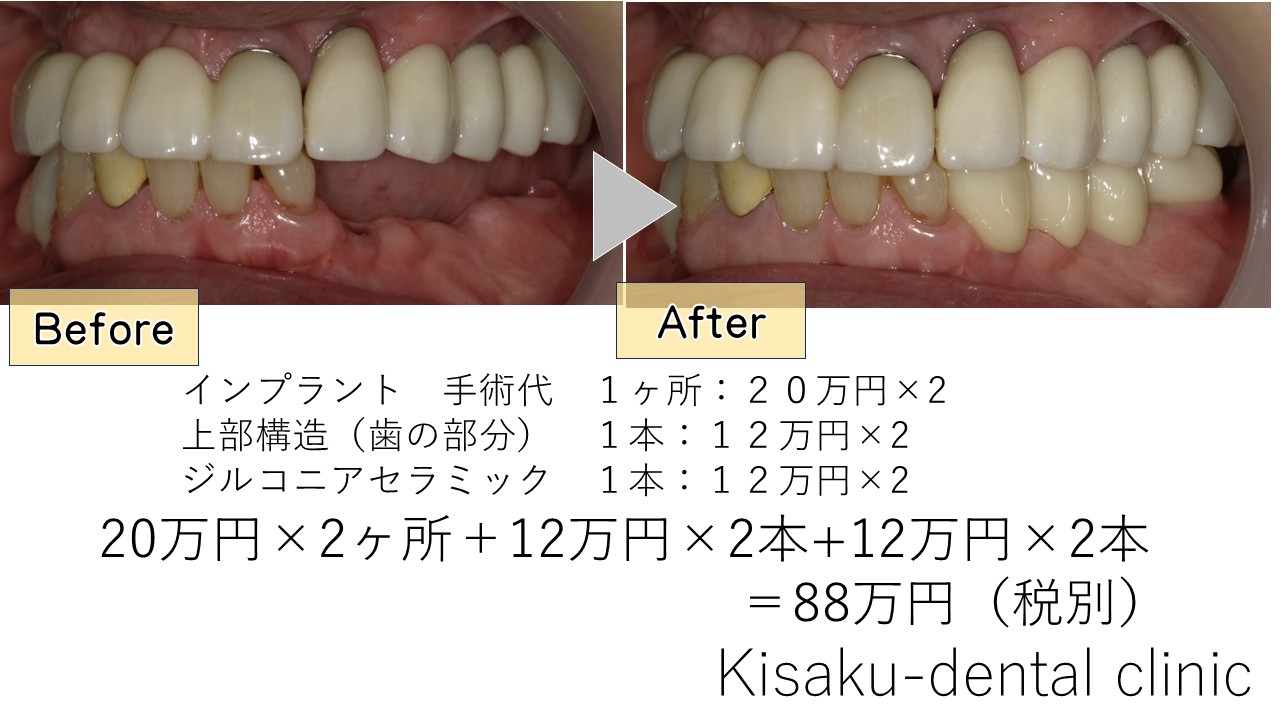

インプラント 手術代 1ヶ所:20万円×2

上部構造(歯の部分) 1本:12万円×2

ジルコニアセラミック 1本:12万円×2

20万円×2ヶ所+12万円×2本+12万円×2本

=88万円(税別)